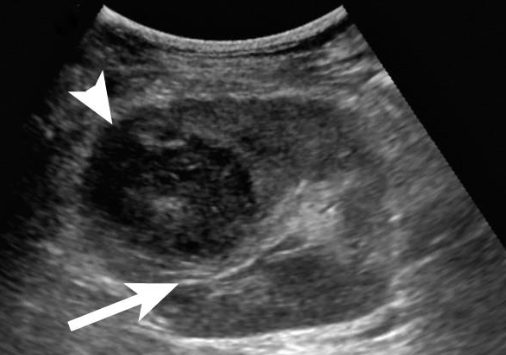

type of renal mass

anechoic, smooth walls, posterior enhancement

Q

Shadowing; characteristics of both cystic and

solid components

A

complex